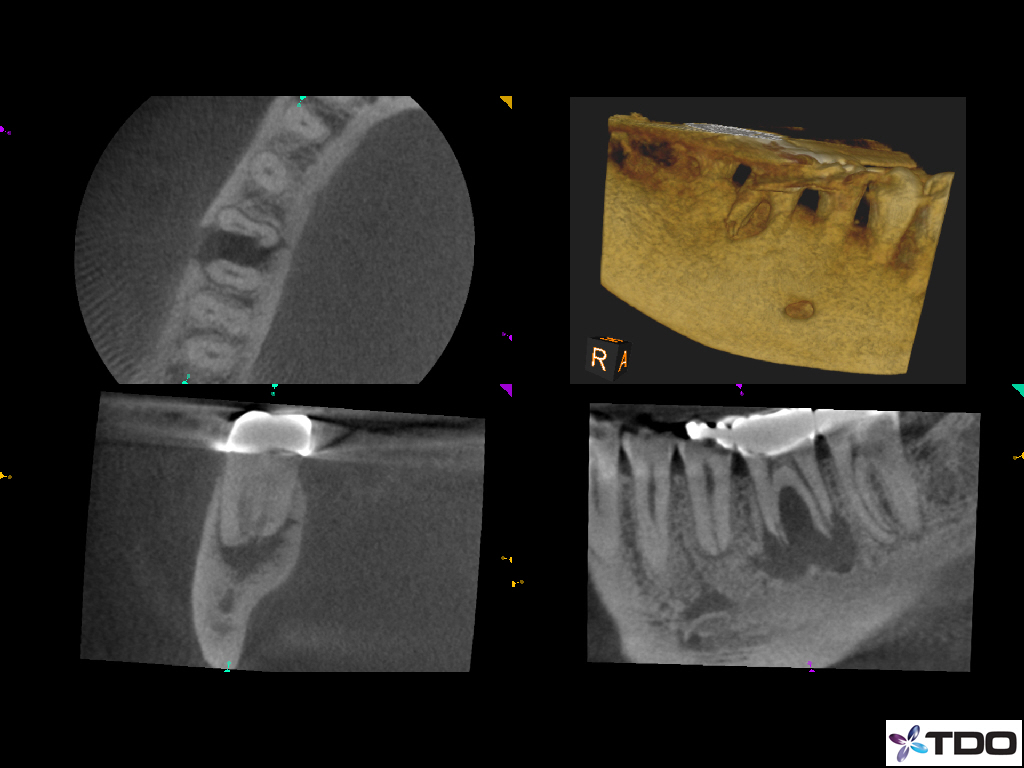

from endoperio.com.br

endofiles • ENDOPERIO